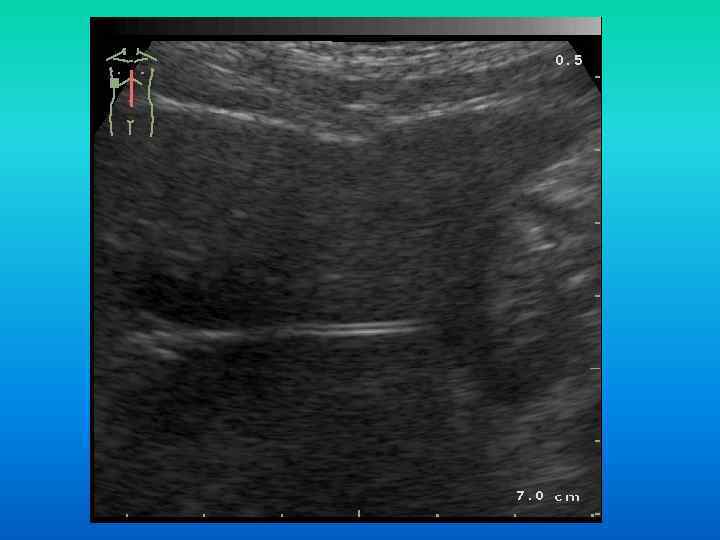

УЗ признаки инородного тела в свободной брюшной полости (большая хирургическая салфетка через 6 мес УЗ признаки инородного тела в свободной брюшной полости (большая хирургическая салфетка через 6 мес после операции):